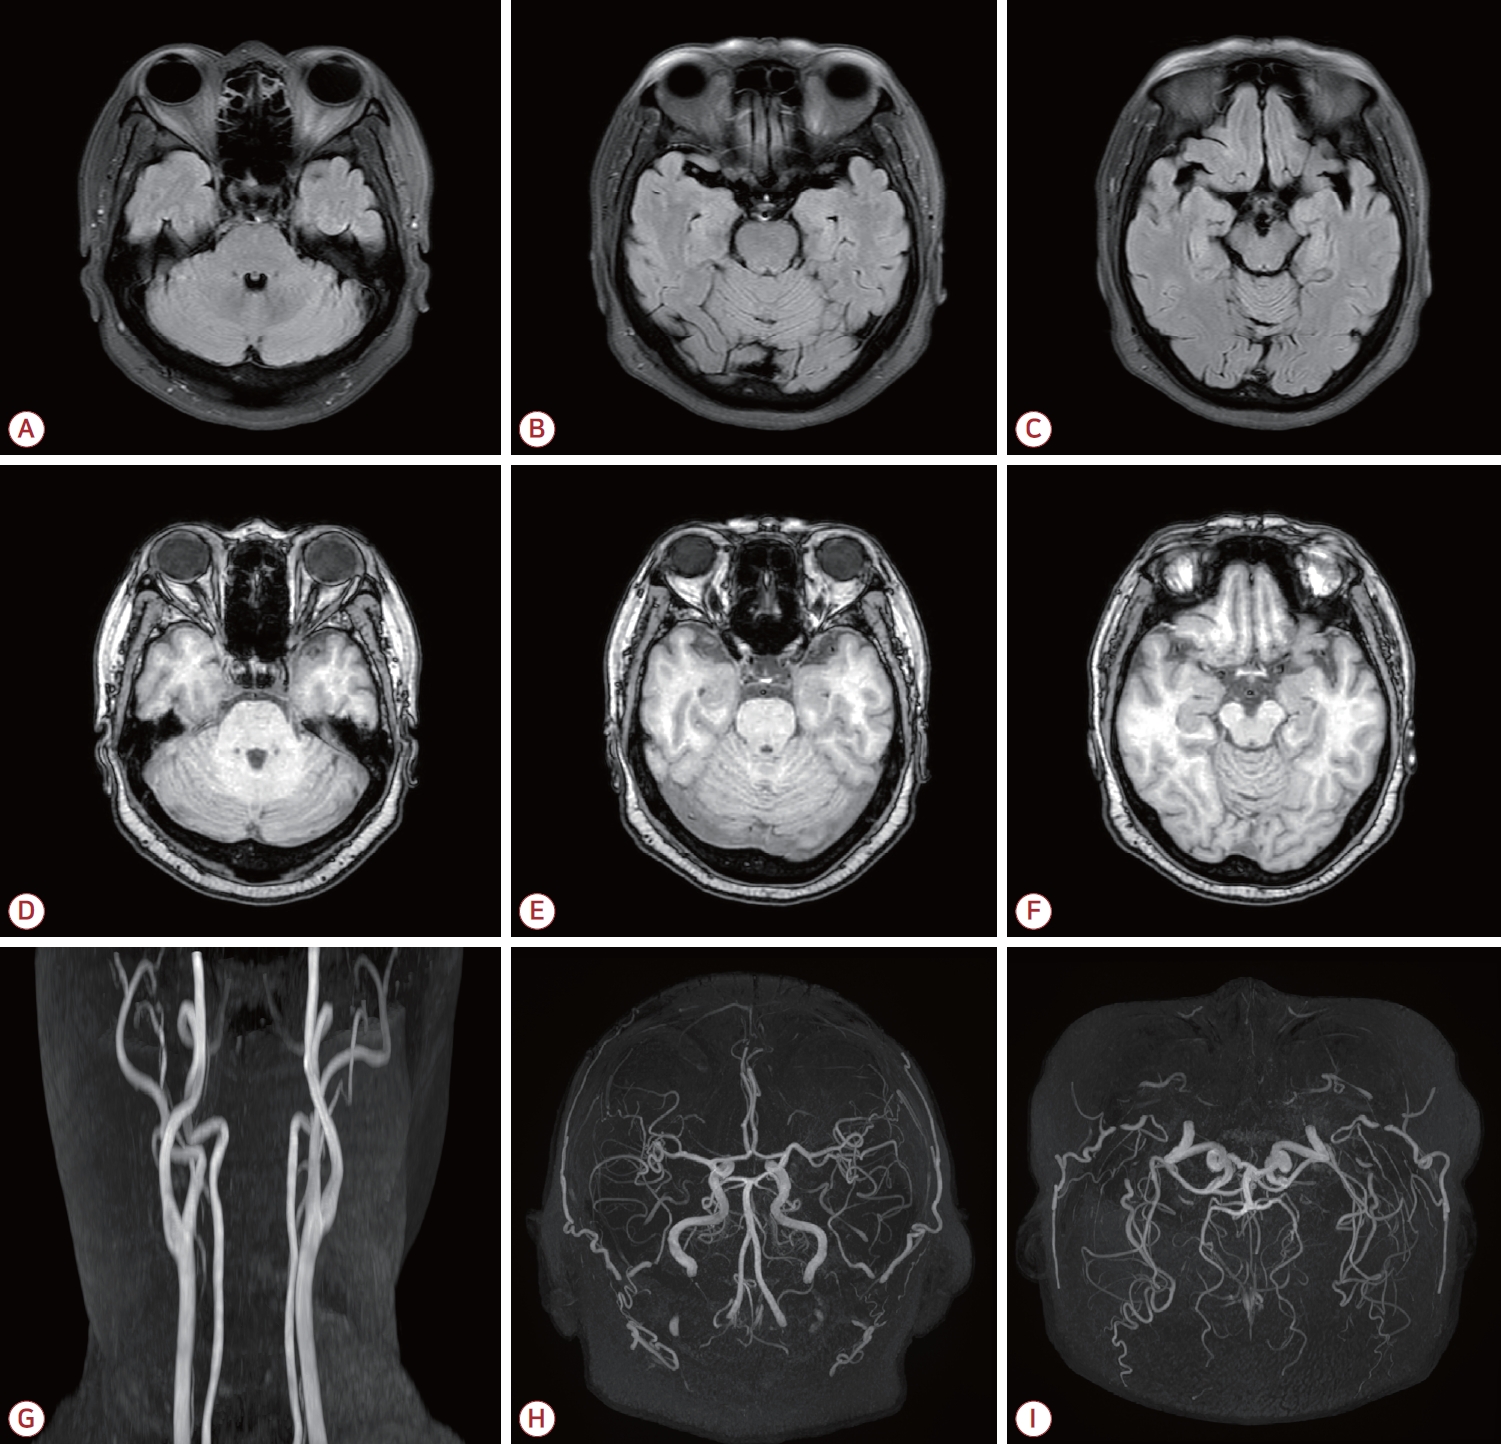

Figure 1.

Brain MRI performed prior to the diagnosis of MPO-ANCA-associated vasculitis demonstrates no abnormal signal on FLAIR images (A-C) or T1-weighted images (D-F). Magnetic resonance angiography (MRA) reveals no significant stenosis or vascular abnormality on carotid MRA (G) or intracranial MRA (H-I). MRI; magnetic resonance imaging, MPO; myeloperoxidase, ANCA; antineutrophil cytoplasmic antibody, FLAIR; fluid attenuated inversion recovery.